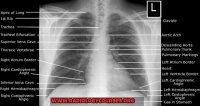

Radiologycourses.org Tips and Hints for the first and Second FRCR anatomy and physics exams. Gallery ….. There are many good courses (Radicon Radiology Courses, FRCR, CT COLON and Other) books and online resources to help you... <a href=" https://www.radiologycourses.org"> FRCR preparation Course Dubai</a>

FRCR preparation course DubaiXray course dubaiRadiology Preparation courses Dubai